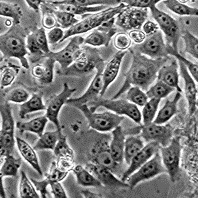

HeLa TK-

Морфология:

эпителиоподобная

Способ культивирования:

монослойный